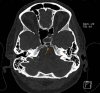

Cerebrospinal fluid (CSF) rhinorrhea is a relatively rare medical condition characterized by the drainage of CSF through the nasal cavity. Cerebrospinal fluid leakage can be attributed to a plethora of different causes, mostly traumatic or iatrogenic, but it can also be spontaneous. Due to its rare entity, CSF rhinorrhea is often a diagnostic trap and can be misdiagnosed and mistreated as rhinosinusitis or allergic rhinitis. This can result in severe complications, such as meningitis, which could potentially have life-threatening consequences if not accurately identified and managed. In this case report, a 53-year-old Caucasian woman presented at the emergency department with symptoms of headache, fever, transparent nasal discharge from her left nostril when leaning forward and mild neck stiffness. Based on the patient's clinical presentation and physical examination findings, there was a high suspicion of central nervous system infection and cerebrospinal fluid leakage. A lumbar puncture confirmed the diagnosis of meningitis, while imaging exams, including computed tomography (CT) and magnetic resonance imaging (MRI) scans, revealed a fistula between the posterior wall of sphenoid sinus and the subarachnoid space. Additional findings included an empty sella turcica, suggesting a potential underlying cause for this condition and an incidental meningioma near the area of leakage. The patient received empiric intravenous antibiotic therapy and was discharged after ten days. She was referred to the neurosurgical department for surgical repair of the CSF leak and removal of the meningioma, in line with appropriate treatment guidelines. This study highlights the importance of promptly identifying and thoroughly investigating potential causes of CSF leakage to provide appropriate medical management.